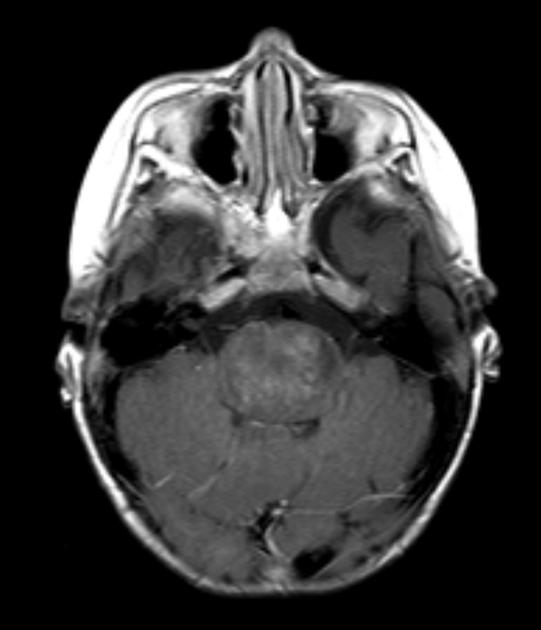

They appear on MRI T2 or FLAIR. The presence of ring enhancement suggests high grade disease. See Radiopedia for more images of diffuse pontine gliomas.

T1/gadolinium